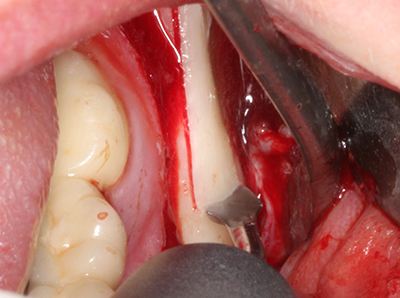

Quando le procedure chirurgiche vengono eseguite sull'osso nelle immediate vicinanze di strutture sensibili, come vasi sanguigni o nervi, gli strumenti rotanti pongono un rischio significativo di lesione iatrogena. I dispositivi piezoelettrici possono essere utili per la preparazione delle coperture ossee e la rimozione del tessuto duro in prossimità dei nervi, in particolare per la loro esposizione dopo una lesione iatrogena, ma anche durante la lateralizzazione dei nervi per le procedure di resezione e ricostruzione o il posizionamento di impianti (figg. 17-20). Il contatto leggero tra puntina piezoelettrica e nervo non causa generalmente danni, ma se si procede senza prestare attenzione con movimenti a sega o raccordi con residui di substrati ossei possono verificarsi danni al nervo temporanei o anche permanenti. Il rischio di danno, tuttavia, è considerato sostanzialmente inferiore al rischio presente utilizzando seghe o frese (Pereira, Gealh et al. 2014).